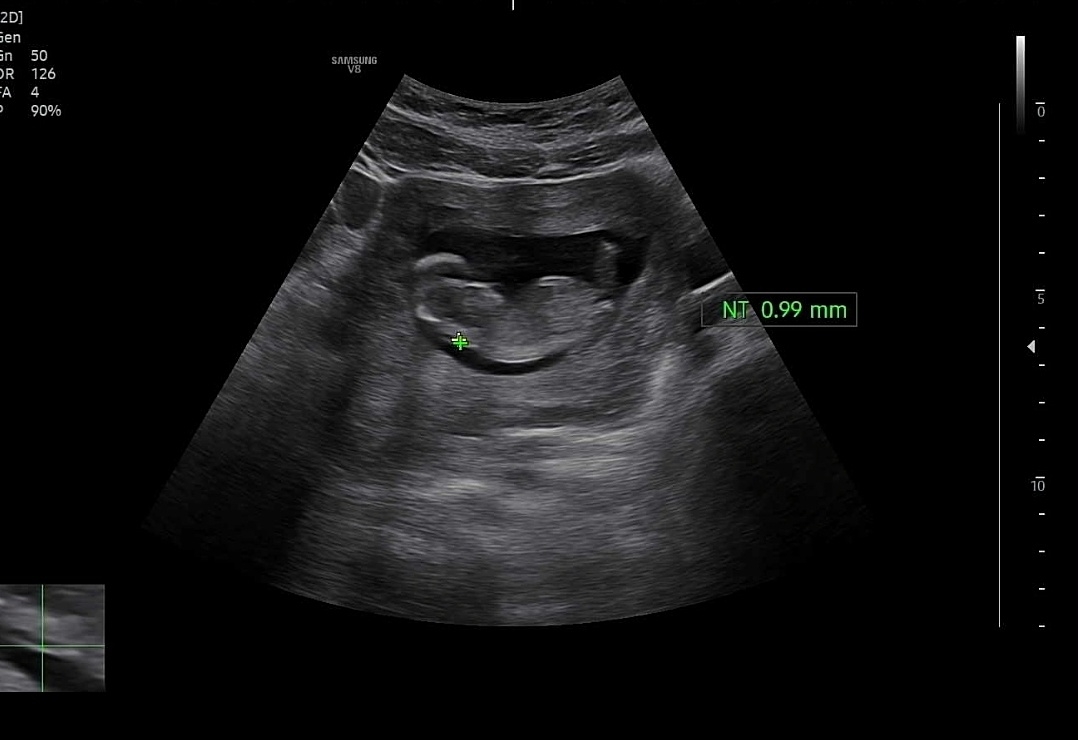

각도법 성별봐쥬세용 ㅠㅠ

12주차 사진인데 초음파 너무 대충해주셔서 사진이 최선이예용 ㅠㅠ 고수님들 부탁드려용